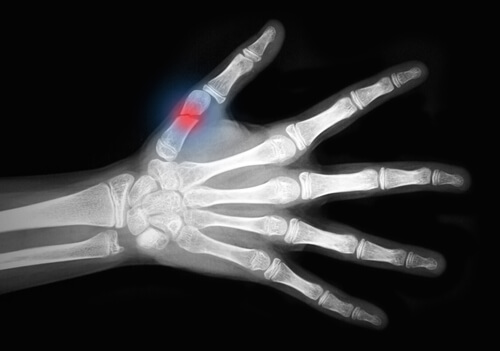

Si tratta di una malattia che indebolisce le ossa, rendendole fragili e soggette alla rottura. Le ossa del polso, dell’anca e della colonna vertebrale sono le più esposte a questo rischio.